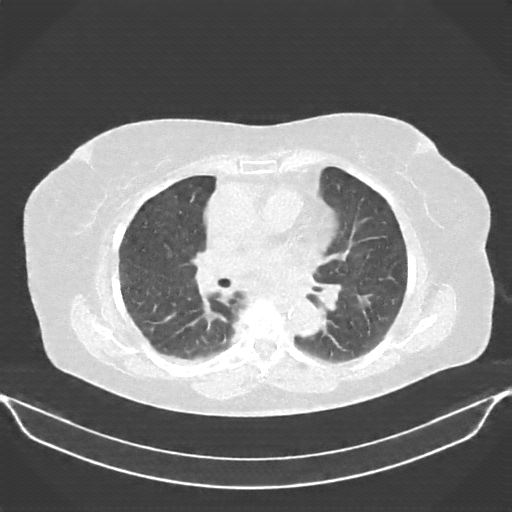

Generated VENOUS CT scan (A→B translation)

No window - Raw intensity values

Lung window (WL -600, WW 1500 β†’ Low βˆ’1350, High +150)

Mediastinum window (WL 40, WW 400 β†’ Low βˆ’160, High +240)